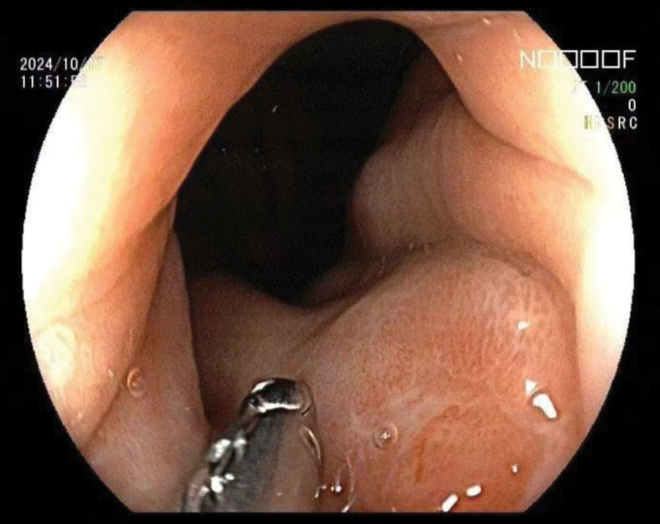

[cite: 59, 60, 61]此外,贲门处也发现一大小约0.6 cm的不规则凹陷性溃疡(图2)。

图2. 贲门处观察到一处不规则的凹陷性溃疡,溃疡底部覆盖着一层黄白色薄膜。周围黏膜充血水肿。标本质地较硬,易出血。